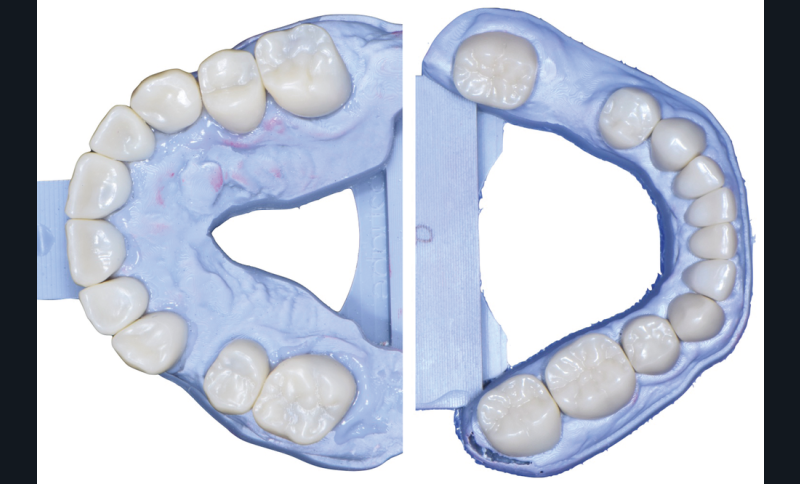

Au vu du contexte para-fonctionnel et de l’étendue de la perte tissulaire, des coiffes périphériques minimalement invasives ont été choisies afin de restaurer l’esthétique et la fonction. Actuellement, aucun consensus n’est fait sur le choix du matériau d’infrastructure à privilégier. Les matériaux hybrides usinables présentent des propriétés mécaniques, physiques et biologiques intéressantes en contexte d’usure sévère (e.g., module d’élasticité, résistance à la propagation de fêlures, facilité de réintervention). Une réhabilitation globale avec remontée de dimension verticale d’occlusion (DVO) par l’intermédiaire de coiffes composites renforcés en nano-céramiques est décrite.